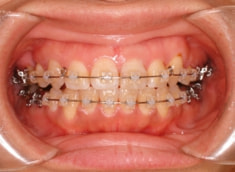

治療後(2年5ヶ月後)

治療開始から約1年2ヶ月後